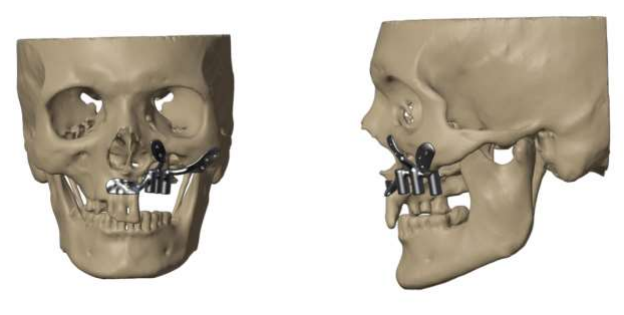

Figure 2: 3D virtual planning of PSI in Mucormycosis case

Figure 2